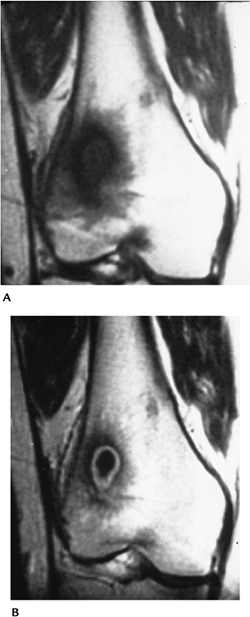

![]() |

FIGURE 11-7 Joint space infection with extension to the epiphysis. (A) Routine radiograph is normal. T2-weighted coronal (B) and sagittal (C) images showing joint effusion and high signal intensity (arrow) in the epiphysis caused by secondary osteomyelitis.